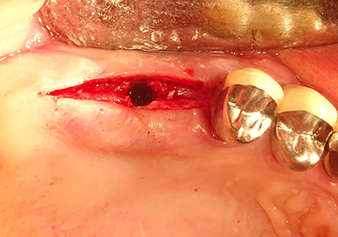

49-летняя пациентка, некурящая и не имеющая ничего примечательного в общей истории болезни, была направлена в нашу хирургическую стоматологическую клинику для хирургического удаления зуба 16 и последующей имплантации. После удаления зуба пациентка перенесла синусит в легкой форме, в результате чего мы сначала выждали шесть месяцев перед проведением операции. Остаточная высота кости при запланированном положении имплантата составляла 3-4 мм (рис. 1 и 2).

Затем, с помощью инструмента I2A (диаметр 2,0 мм), дно пазухи перфорировалось периодически и в минимально возможном диапазоне. Этот специфический пьезохирургический метод гарантирует, что мембрана Шнейдера не будет повреждена. При использовании Z25P, мембрана уже была слегка приподнята охлаждающей жидкостью, подаваемой через наконечник инструмента (рис. 3). Во избежание высокого давления в ложе имплантата, количество охлаждающей жидкости составляло не более 50%.